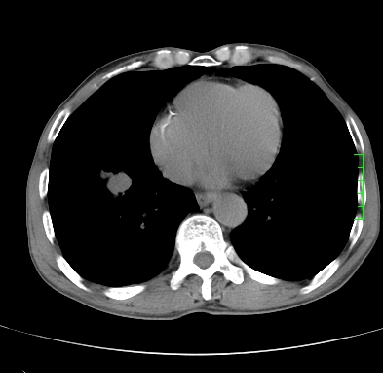

m,73y。膝关节疼痛伴双下肢水肿。入院常规胸片发现结节灶。增强为静脉期。

浅分叶、棘突,考虑右下肺周围型肺癌

考虑周围型肺癌  ,双上肺结核。

肿块周围可见局限性气肿,考虑肺癌可能性大。双肺上叶继发型肺结核。

指套征,强化明显,近侧肺组织局限性肺气肿,考虑支气管类癌,慢支、肺气肿、双上陈旧性tb、冠脉钙化。

鉴别:先天性支气管闭锁,变态反应性支气管肺曲霉菌病,肺癌,支气管囊肿,支扩黏液嵌塞。

1)考虑右肺下叶周围型肺癌。2)右肺上叶及左肺感染性病变(结核可能)。3)肺气肿。4)冠状动脉钙化。